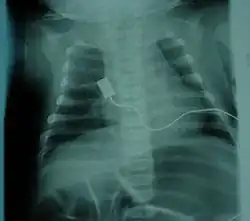

![]() | |

| Location of neurons affected by spinal muscular atrophy in the spinal cord | |